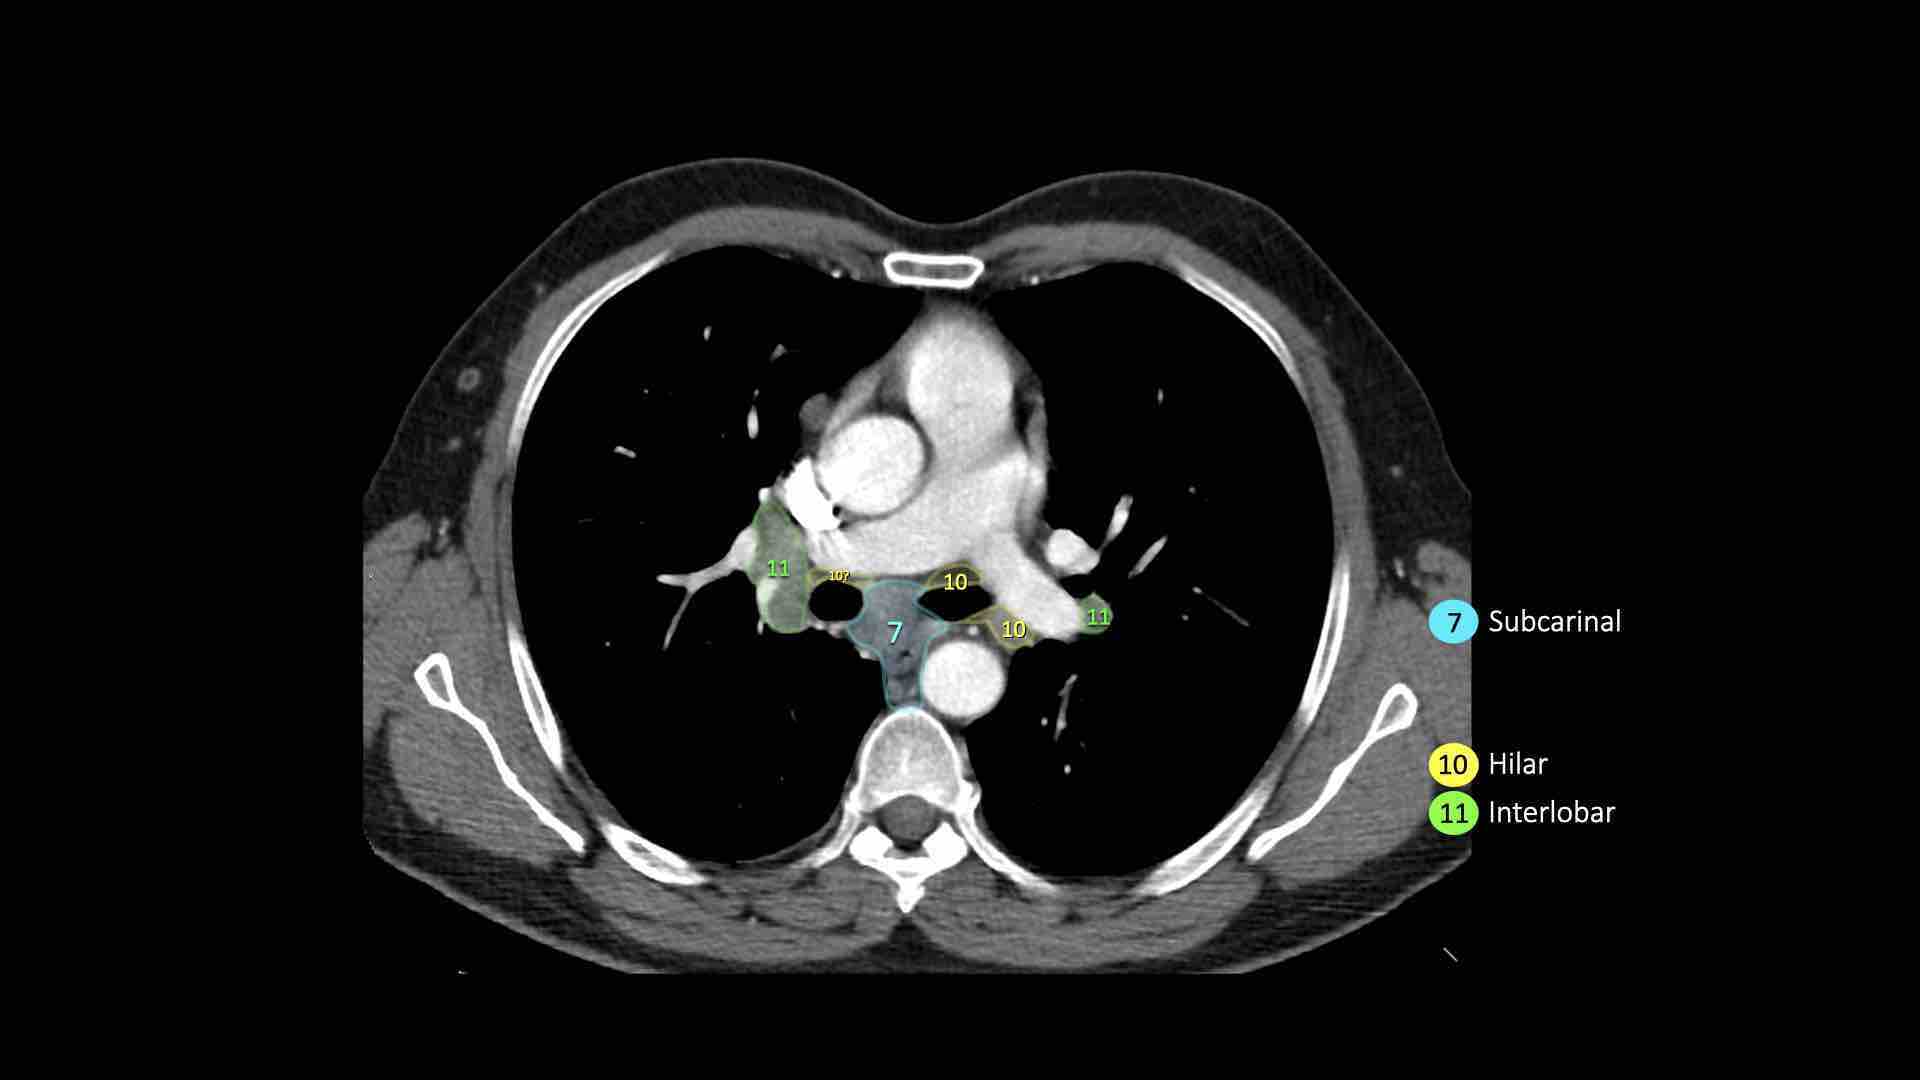

7.Dưới carina

7. Hạch dưới carina

Các hạch này nằm ở phía dưới carina khí quản, nhưng không liên quan đến phế quản thùy dưới hoặc các động mạch trong phổi.

Bên phải, chúng trải dài xuống đến bờ dưới phế quản trung gian.

Bên trái, chúng trải dài xuống đến bờ trên phế quản thùy dưới.

10. Hạch rốn phổi

Bao gồm các hạch tiếp giáp với phế quản gốc và các mạch máu rốn phổi.

Bên phải, trải dài từ bờ dưới tĩnh mạch đơn đến vùng gian thùy.

Bên trái, từ bờ trên động mạch phổi đến vùng gian thùy.

Hạch rốn phổi là các hạch thùy gần, nằm ở phía xa so với nếp gấp màng phổi trung thất và các hạch kề phế quản trung gian bên phải.